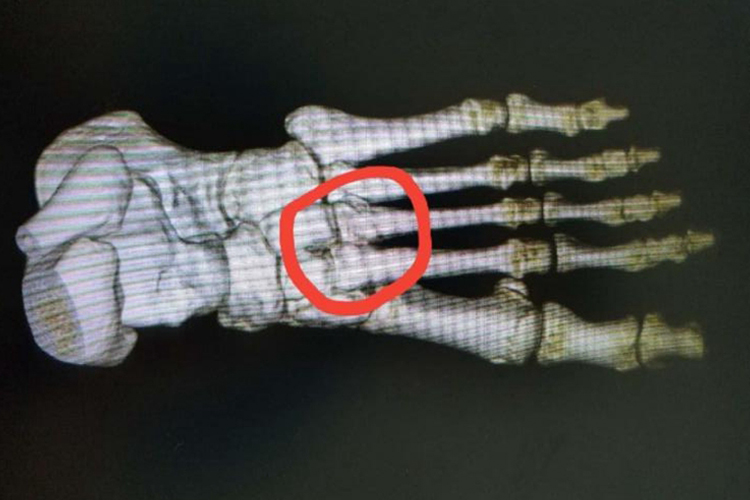

左脚第二三跖骨骨折患者会出现局部疼痛、肿胀以及活动受限,X线检查可明确诊断。

左脚第二三跖骨骨折患者通常表现为疼痛、肿胀和足背中部局限的压痛。因足屈肌腱的牵拉,远端骨折块往往向跖侧和近端移位。X线片通常用于该种骨折的诊断。